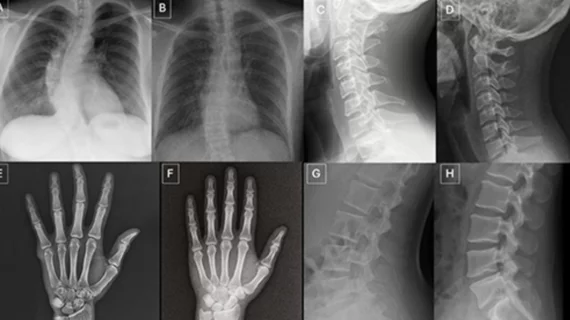

This page includes content on healthcare management, including health system, hospital, department and clinic business management and administration. Areas of focus are on cardiology and radiology department business administration. Subcategories covered in this section include healthcare economics, reimbursement, leadership, mergers and acquisitions, policy and regulations, practice management, quality, staffing, and supply chain.